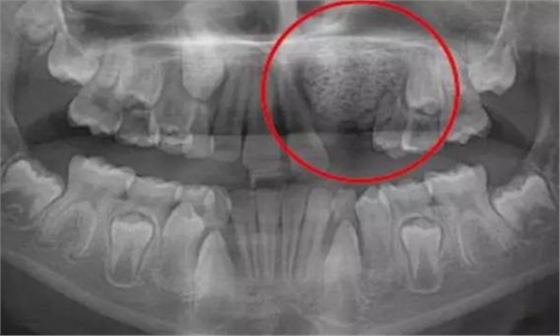

一名 23 區(qū)的9歲患者,在診所接受檢查時(shí)發(fā)現(xiàn)口內(nèi)中存在大范圍含牙囊腫[圖1]。由于上頜竇下沿出現(xiàn)大范圍突出,迫切需要接受囊腫去除手術(shù)[圖2和3]。

囊腫去除[圖2]

囊腫去除后的大量骨缺損[圖3]